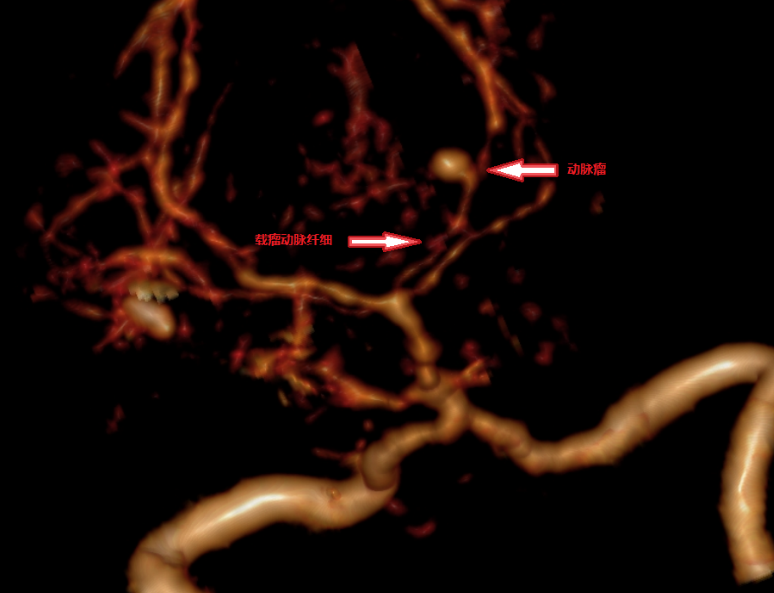

??入院后,为明确孙先生多次脑出血的原因,复查颅脑CT并急查颅脑动脉CT血管成像,显示其左侧大脑后动脉P2段有动脉瘤,且动脉瘤已破裂并破入脑干,左侧基底节出血,出血量约为30毫升,情况十分危急。

??术前CTA

??颅脑CTA原始图像示动脉瘤与血肿关系密切

??脑动脉瘤